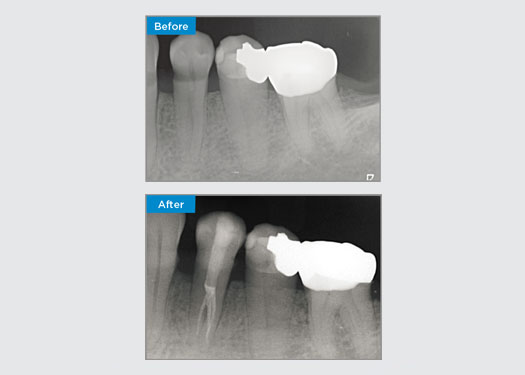

The patient was presented with irreversible pulpitis on tooth 46. From the pre-op radiograph, tooth 46 is presented with an additional distal root (Radix Entromolaris tooth morphology). A CBCT scan has confirmed the presence of DL root with severe root curvature. A careful file selection is critical for this delicate DB root.

Dr Jack Lin, Endodontist, Sydney, NSW Australia